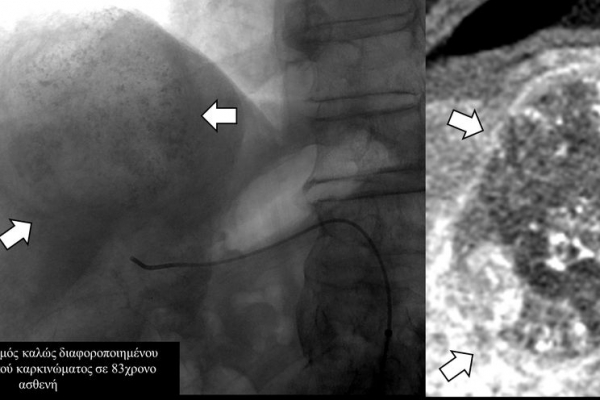

Ο χημειοεμβολισμός έχει καθιερωθεί σαν θεραπεία εκλογής στο ενδιάμεσο στάδιο του ηπατοκυτταρικού καρκινώματος.

Ενδείξειςαποτελούν επίσης το χολαγγειοκαρκίνωμα και οι μεταστάσεις από καρκίνο του μαστού, καρκίνωμα νεφρού και σαρκώματα μαλακών μορίων.